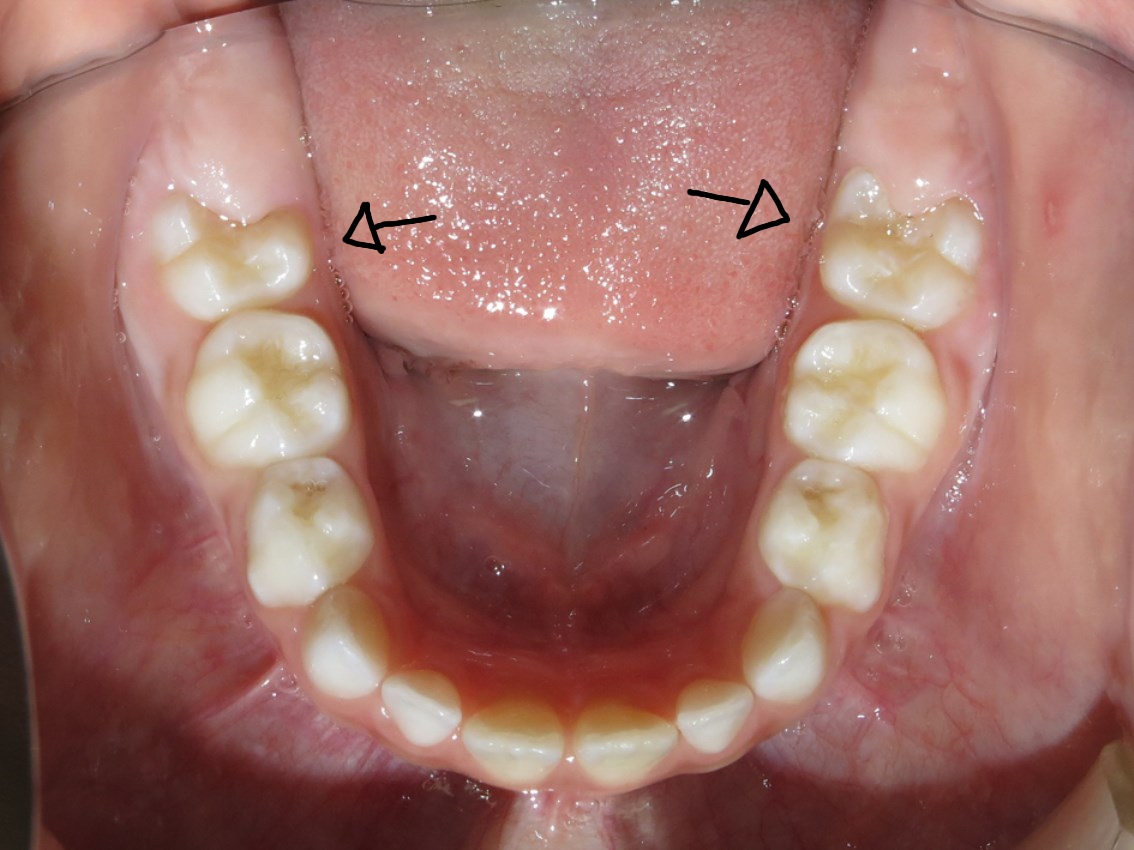

Odontologando: Dentes permanentes nascendo atrás dos dentes de leite. É

WebDente permanente nascendo atrás do dente de leite. Quando as crianças estão entre os cinco e os doze anos de idade, elas passam pelo processo de mudança da dentição.. WebOs primeiros dentes do bebê costumam surgir no primeiro ano de vida e, até completar 3 anos de idade, a criança já deve estar com a dentição completa. Na faixa de. Web0:00 / 5:40 Dente permanente nascendo antes do dente de leite cair? 30,992 views Jul 3, 2020 1.4K Dislike Share Dra Letícia Ramadan Essa situação já aconteceu contigo? Cada. Webmarço 2021 A hiperdontia é uma condição rara na qual surgem dentes extra na boca, podendo acontecer na infância, quando surgem os primeiros dentes, ou durante a. WebTAGS: DENTES NASCENDO POR TRÁS, DENTES QUE NASCEM ATRÁS. Uma causa comum no consultório de Odontologia Pediátrica é o nascimento dos dentes. WebTenho 23 anos e notei que está nascendo um novo dente abaixo do ultimo siso do lado direito da minha. 5 respostas. Tenho 23 anos e notei que está nascendo um. WebSonhando sonhar com dente caindo e nascendo outro no lugar pode significar uma significativa positiva ou negativa para sua vida. Dependendo de onde você ver o seu. WebO colar mordedor é do tipo 2 em 1: ajuda a compor o visual da mãe e serve para o bebê coçar as gengivas e aliviar a dor quando o dente está nascendo (serão muitos meses.